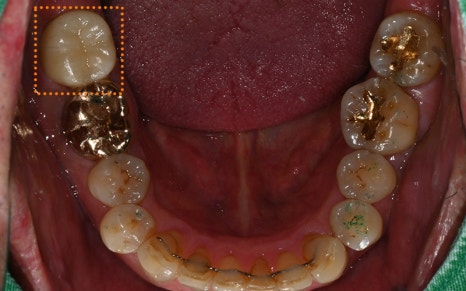

✅ 치료 완료 후 보철물까지 완성!

교합을 섬세하게 고려하여

정밀하게 보철작업까지

완료된 모습입니다!